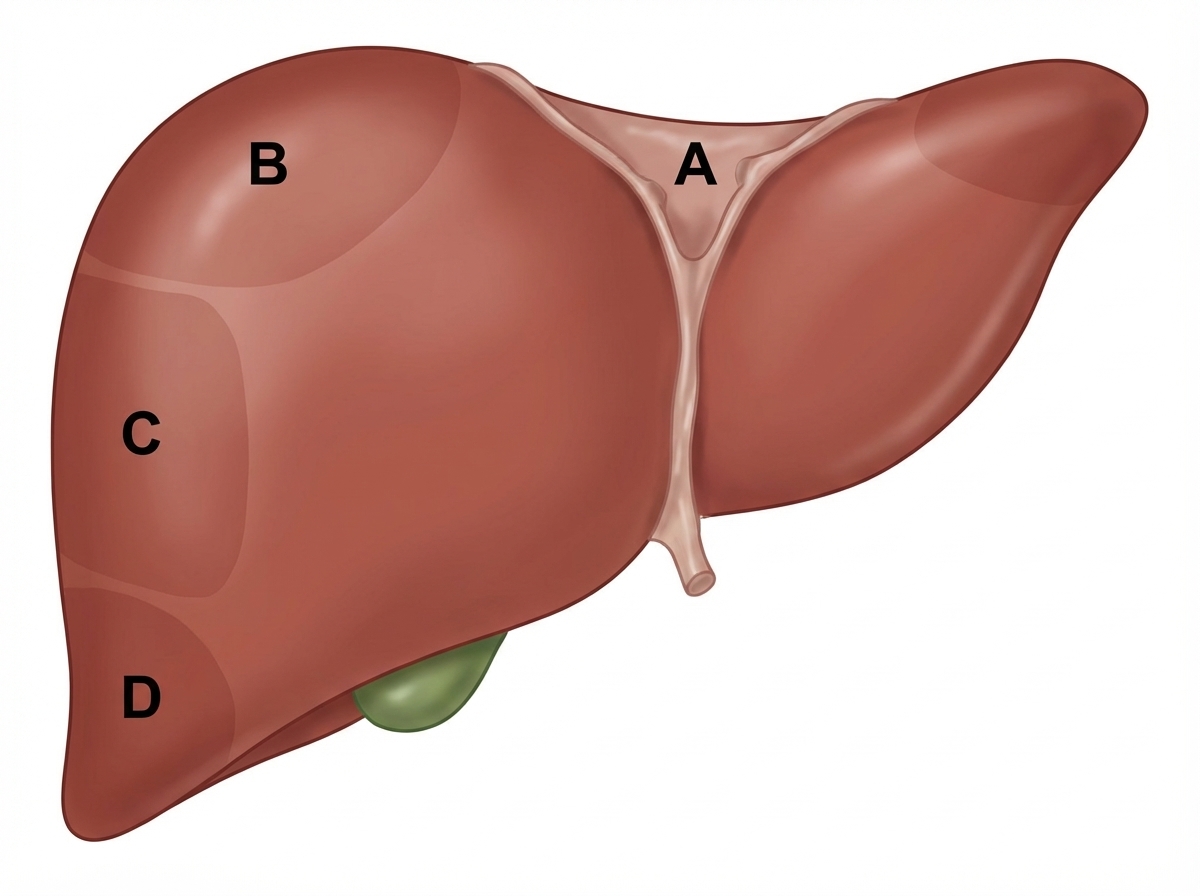

Which of the following is the bare area of liver?

Explanation: ***Correct: Option A*** - This area represents the **bare area of the liver**, which is the posterior surface of the right lobe that is directly in contact with the diaphragm - This region is **NOT covered by peritoneum** (visceral or parietal) - It is bounded by the **superior and inferior layers of the coronary ligament** - Laterally bounded by the **right and left triangular ligaments** - Clinical significance: This direct contact with the diaphragm allows for potential spread of infection between the liver and thoracic cavity *Incorrect: Options B, C, D* - These represent other surfaces or areas of the liver that are covered by visceral peritoneum - All other liver surfaces (anterior, superior, inferior, and most of posterior) are covered by peritoneum except the bare area